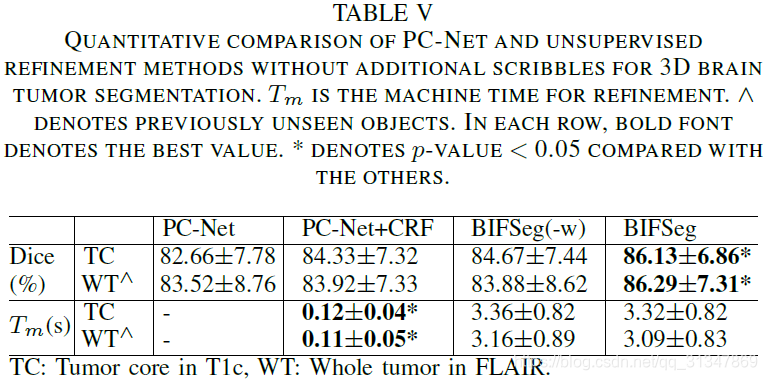

比较 BIFSeg 和 1)P-Net/PC-Net 的初始分割结果;2)用 CRF 处理之后的分割结果;3)BIFSeg(-w) 的分割结果(基于 Eq(1),所有像素的权重 w ( i ) = 1 w(i) = 1 w(i)=1),以及其他交互式分割方法:用于 2D 分割的 GrabCut,SlicSeg,Random Walks;用于 3D 分割的 GeoS,GrowCut,GrabCut 3D

2. 3D 图像分割

(2)Unsupervised Image-specific Fine-tuning:

基于 PC-Net 得到的初始分割结果,仍然用其他三种方式进行无监督的调整。

不管对于见过的还是没见过的图像,BIFSeg 仍然是表现最好的,其他两种方法相比初始结果有提升,但是不够好。